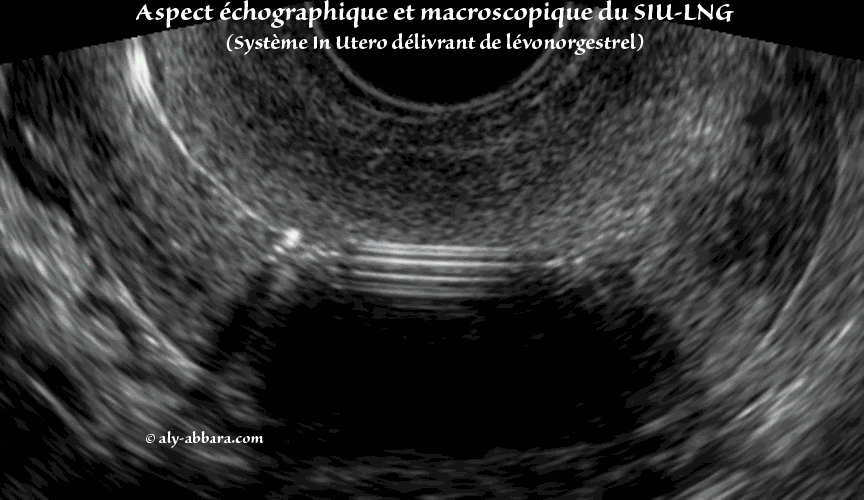

• Images montrant l'aspect échographique de l'ensemble des éléments composant la tige verticale du stérilet hormonal (ou le système in-utero délivrant de lévonorgestrel " SIU-LVN "). Ces images échographiques sont ensuite comparées aux aspects macroscopiques du même stérilet.

• En effet, ce système de contraception hormonale à effet local est composé :

• du réservoir hormonal contenant le progestatif (52 mg de lévonorgestrel) se trouvant autour de la tige verticale du dispositif intra-utérin ;

• ce réservoir est recouvert par une membrane de diffusion (manchon) composée de : polydiméthylsiloxane (Élastomère 4910), polydiméthylsiloxane (PDMS 373 M) ;

• Le corps en T : polyéthylène, sulfate de baryum ;

• Le fil de retrait : polyéthylène, oxyde de fer.

• La libération du lévonorgestrel à partir du DIU est d'environ 20 µg/24 heures. Le lévonorgestrel est administré directement dans la cavité utérine, ce qui conduit à une dose journalière très faible, l'hormone étant libérée directement dans l'organe cible.